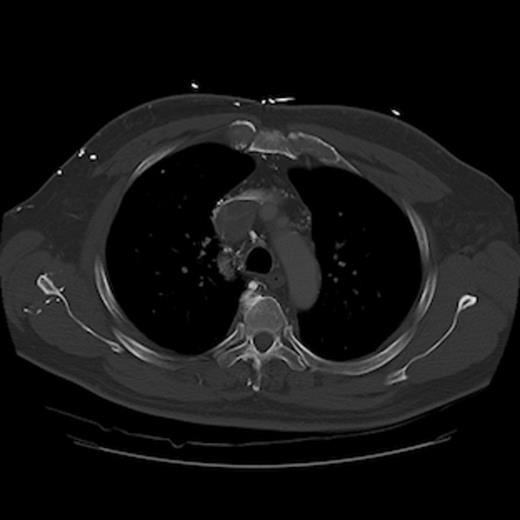

A 67-year old gentleman presented with progressive head and neck swelling and discomfort for several months. His symptoms were pronounced by bending over or straining in the bathroom. His symptoms worsened and he was referred for thoracic surgery consultation after a mass was seen on chest x-ray. He was diagnosed with SVC syndrome secondary to a mediastinal mass, demonstrated best by computed tomography (CT) [Figures 1, 2, 3].

CT of the chest (coronal section) with intravenous contrast: demonstrates complete obstruction of the superior vena cava by a large intramural thrombus that extends into brachiocephalic vein